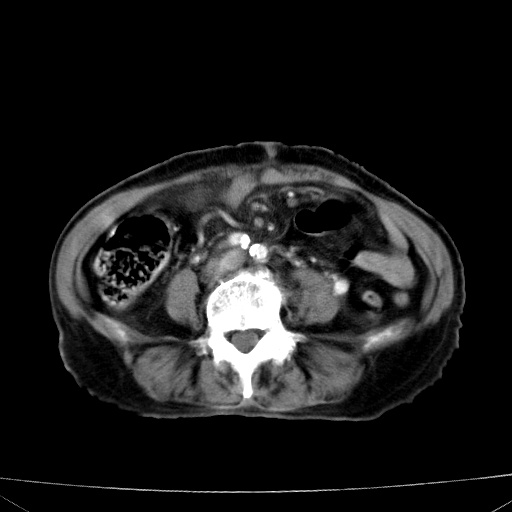

网站人气太旺!昨天的帖子就沉到海底,只好再发贴!ct18338:女 78岁,肝胆病变,已增强,再会诊!原帖链接:http://www.radida.com/bbs/forum.php?mod=viewthread&tid=50032

1)考虑胆囊癌侵犯肝脏并肝门区、腹膜后及右侧膈角后淋巴结转移。2)肝左叶近肝顶部囊肿。3)肝左叶肝内胆管结石。4)左肾近下极囊肿。

1、胆囊癌侵犯肝脏并腹腔及腹膜后淋巴结转移。

2、肝左叶外侧段囊肿。